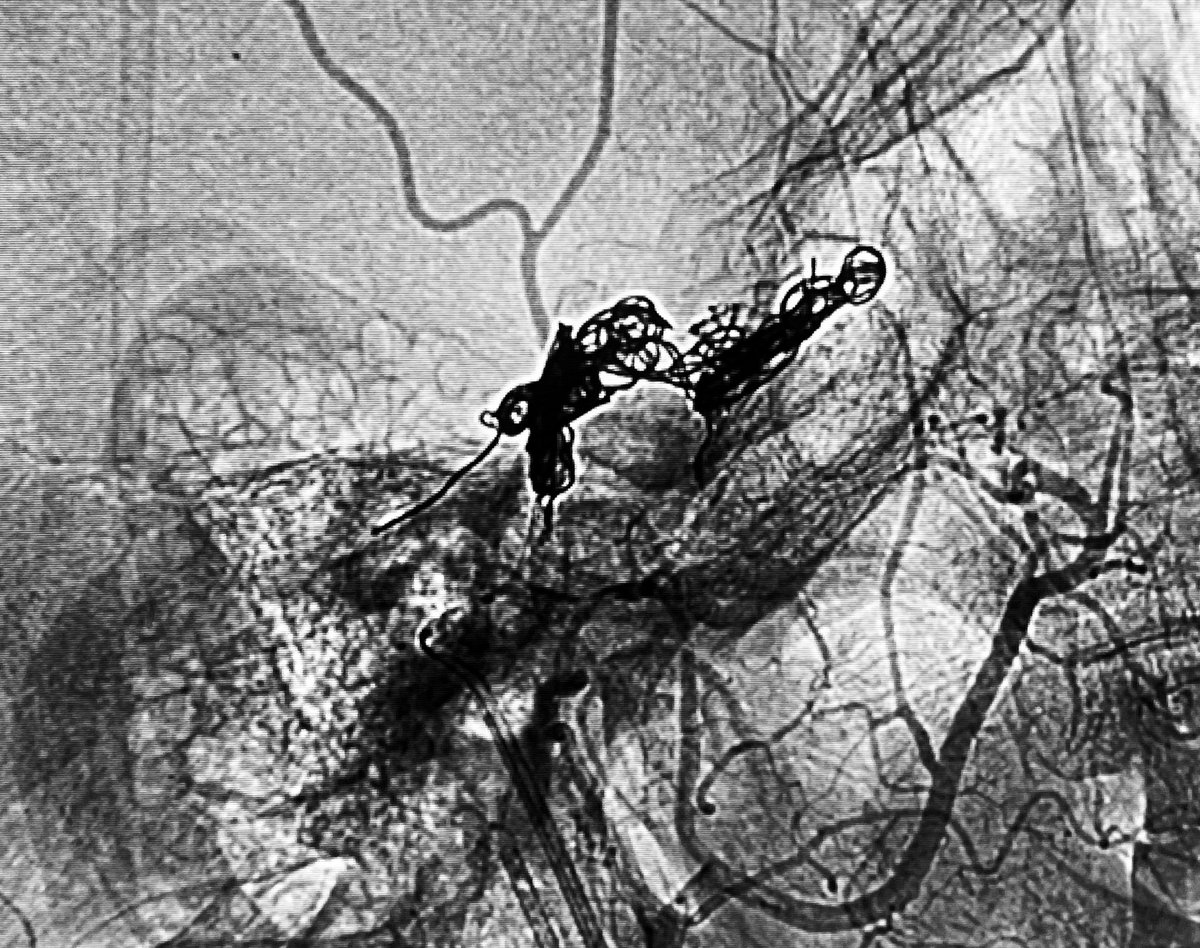

Onyx–Coil remains the best option in this case, used to embolize a bleeding AComA aneurysm–pseudoaneurysm. #CoilOnyx #NeuroIntervention #StopBleeding